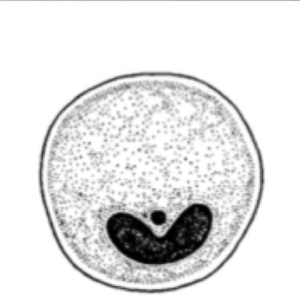

Parasitic cysts are spherical to ovoid and measure 50 to 100 µm in diameter. Their outer membrane is thick, and they have a granulomatous content. A macronucleus and a micronucleus are present, but often difficult to visualize (Strait et al., 2012). Lugol staining allows the visualization of some organelles, which are colored in dark brown. It also allows the coloration of the outer membrane in brown and of the inside of the cyst in cream.